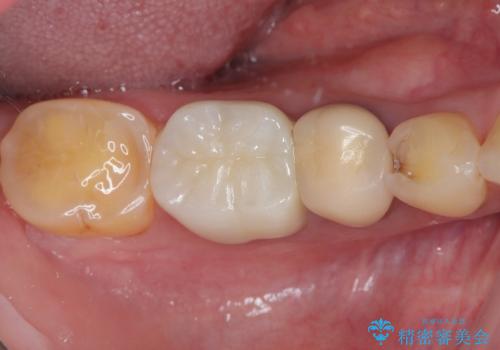

検診で見つかった齲蝕のセラミックインレー修復

- 検診で初期の齲蝕が見つかった患者様です。

これ以上神経の治療や被せものになりたくないため、初期のうちにしっかりとした治療をしたいとのことでした。

齲蝕をしっかりと除去して、精度の高いシリコーンによる型どりを行いセラミックインレーで修復しました。

唾液による接着阻害を防ぐために、ラバーダム防湿を行っています。